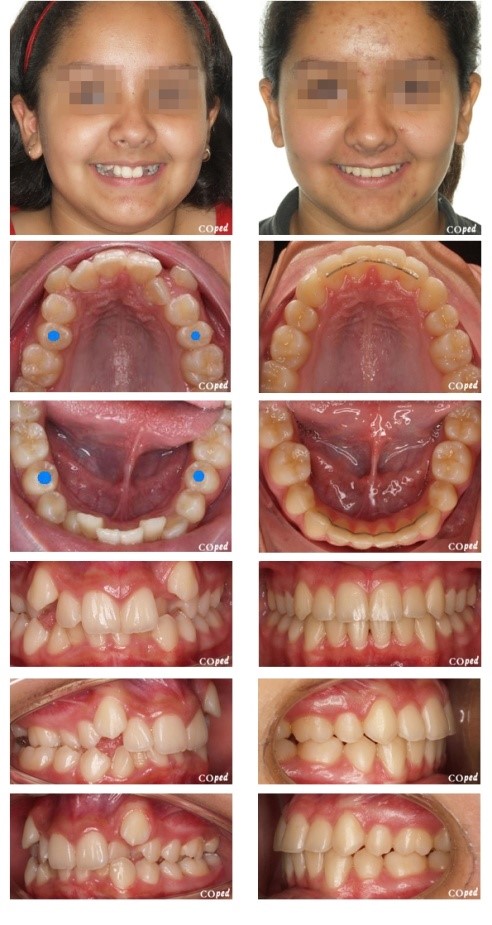

- Apiñamiento dental severo

- Protrusiones dentoalveolares

- Apiñamiento dental severo

Protrusiones dentoalveolares.